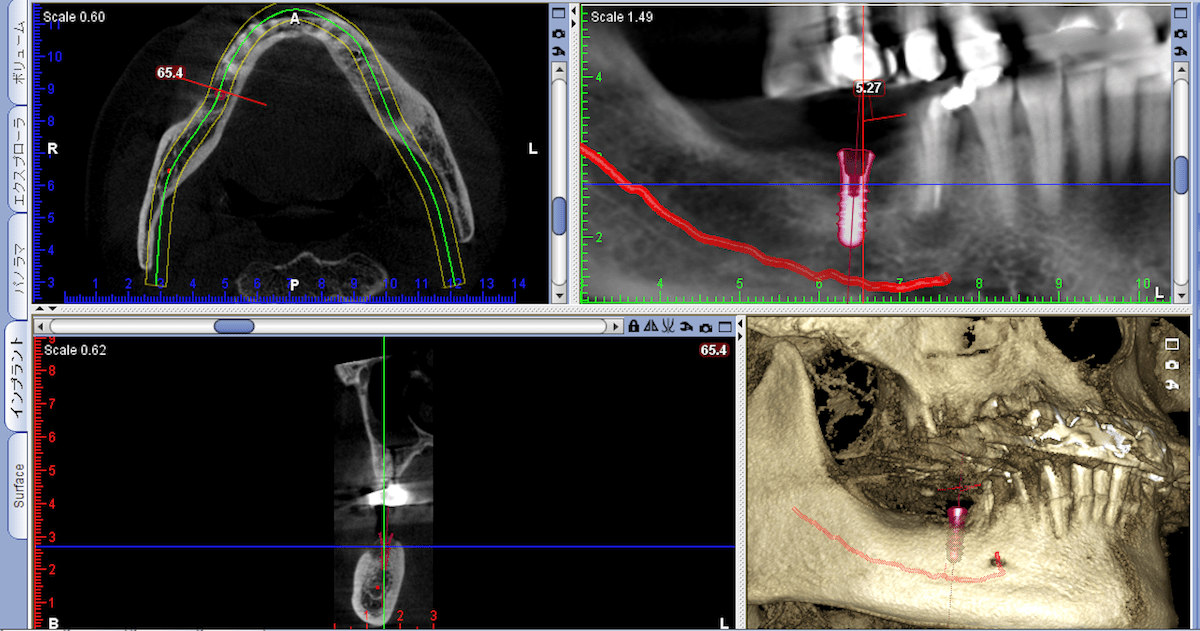

従来のレントゲンでは把握できなかった歯や骨の状態、神経・血管の走行などを、

精密な3D画像により確実に診断することができます。

インプラントや親知らずの抜歯などの外科処置、根管治療には非常に有効です。